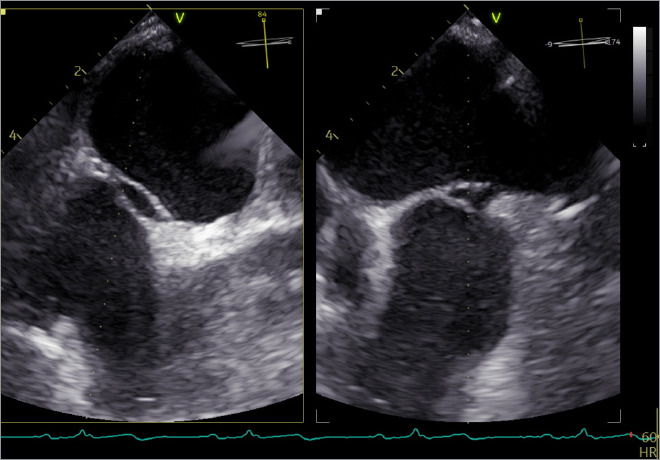

Double Atrial Septum With Interatrial Space in Patients Experiencing Ischemic Attack.

双房间隔伴房间隙与缺血性发作的关系。